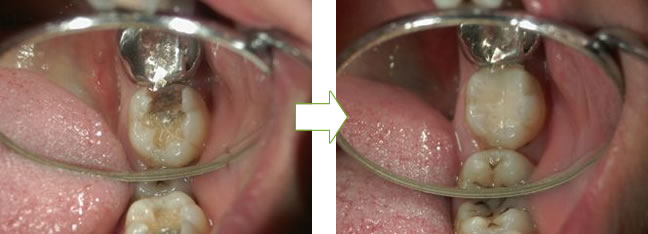

befor after

befor → ドックベストセメントを入れる → after